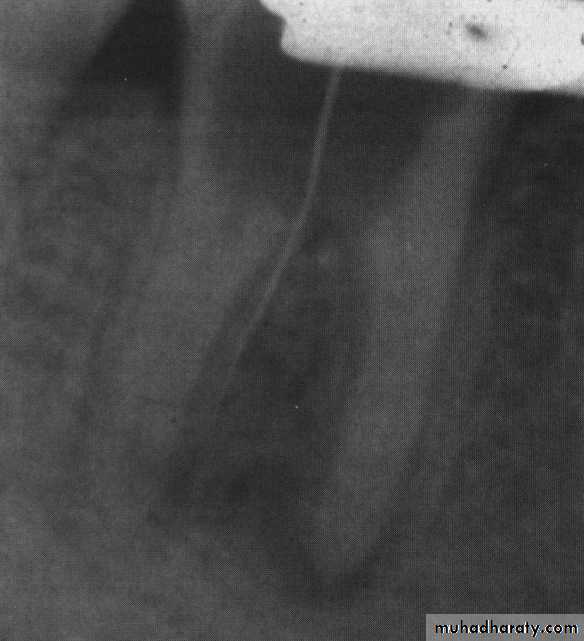

Bur held alongside radiograph to estimate the depth

of penetration